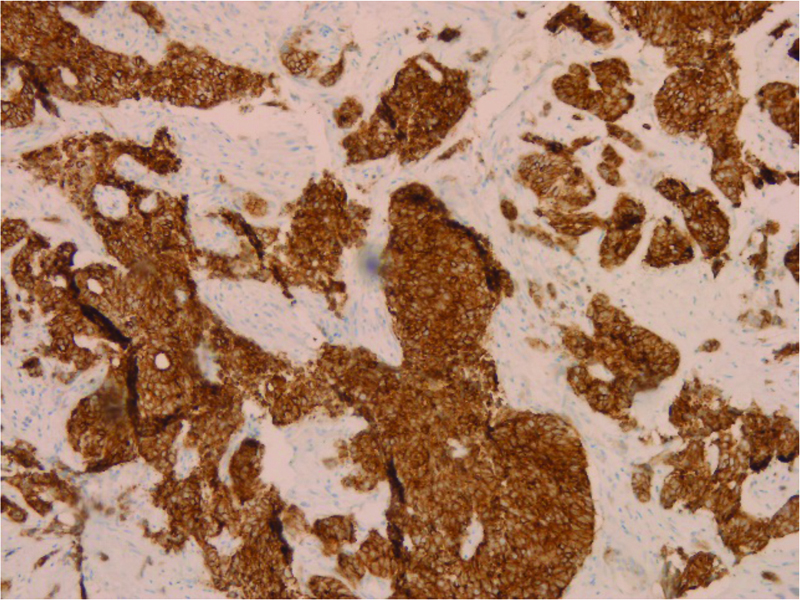

The biopsy showed a biphasic tumor, composed of ductal and myoepithelial cells in a solid pattern with basaloid appearance, high mitotic rate and marked nuclear atypia, supporting high grade transformation (Figure B&C). The tumor was strongly and diffusely positive for immunohistochemical stains CK7 (Figure D) and CD117 (Figure E). Molecular studies were also performed, and the tumor showed t (6;9) MYB-NFIB fusion which is characteristic and diagnostic for adenoid cystic carcinoma in 60–90% of the cases. Overall, the findings were consistent with high-grade adenoid cystic carcinoma, solid type.

Figure D

Figure D. Positive for immunohistochemical stain CK7, highlighting the ductal component of the tumor.